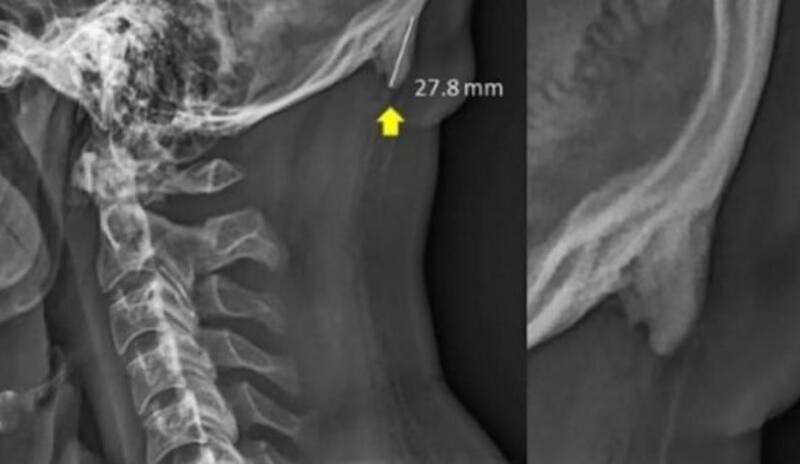

Los científicos australianos analizaron más de mil cráneos de personas de entre 18 años y 86 años con imágenes de rayos X antes de arribar a esta curiosa conclusión.

Los investigadores destacaron que ambos factores permitieron el desarrollo de un sobrehueso en la parte posterior de nuestros cráneos.